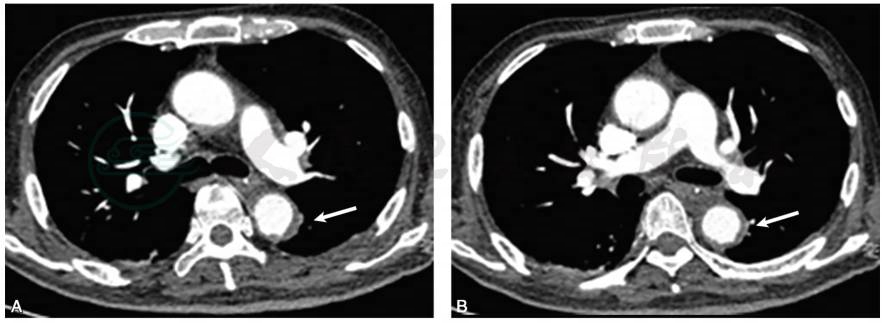

出院后1个月随访,胸闷、气短症状明显减轻,体温维持正常。2017年4月7日复查肺动脉CTA示(图2):主动脉弓及降主动脉管壁增厚,形态不规则,符合大动脉炎表现。与2017年2月22日肺动脉CTA比较,胸主动脉管壁已明显变薄。肺动脉部分分支远端充盈缺损。双侧胸腔积液已吸收。

图2 患者口服激素1个月余,复查肺动脉CTA示:胸主动脉管壁明显变薄,管腔仍然不规则(白箭)